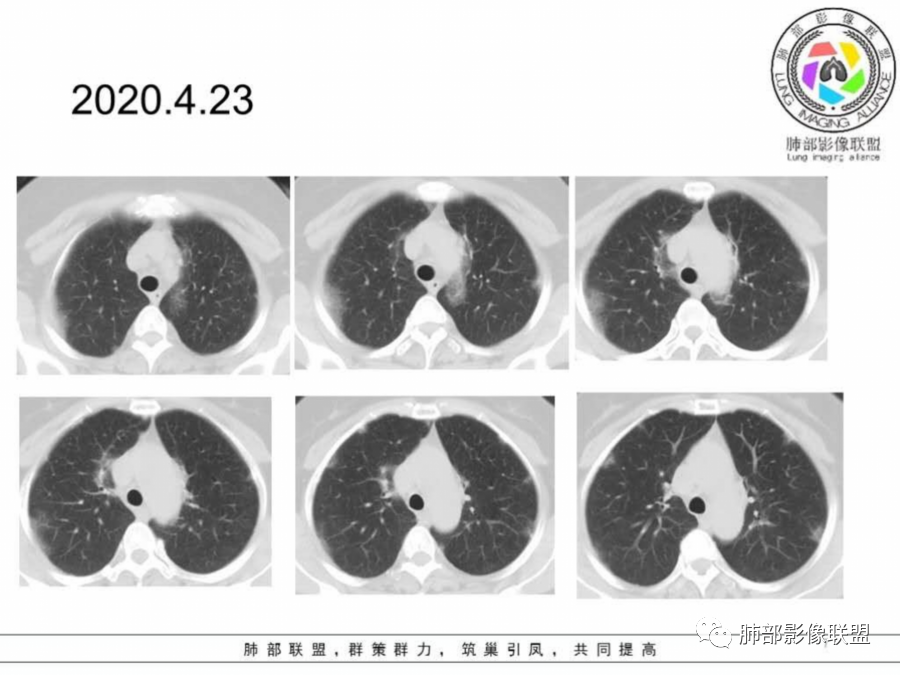

胸CT:4月23:双下肺渗出影,以外周胸膜下为主,4月29日病灶增多,部分沿支气管血管束分布,渗出影病灶密度较前增高。

胸CT:4月23日:支气管血管束及胸膜下分布实变及磨玻璃影,4月29日病灶增多。

两肺胸膜下外周为主多发磨玻璃影、实变影,非叶段分布,间质受累,抗感染治疗效果不佳。

这个病变其实也就是周围间质的病变,有细网格征及碎石路征,这是典型的OP样改变,外围胸膜下,下肺明显,有一定的此起彼伏,影像只能判断到OP。